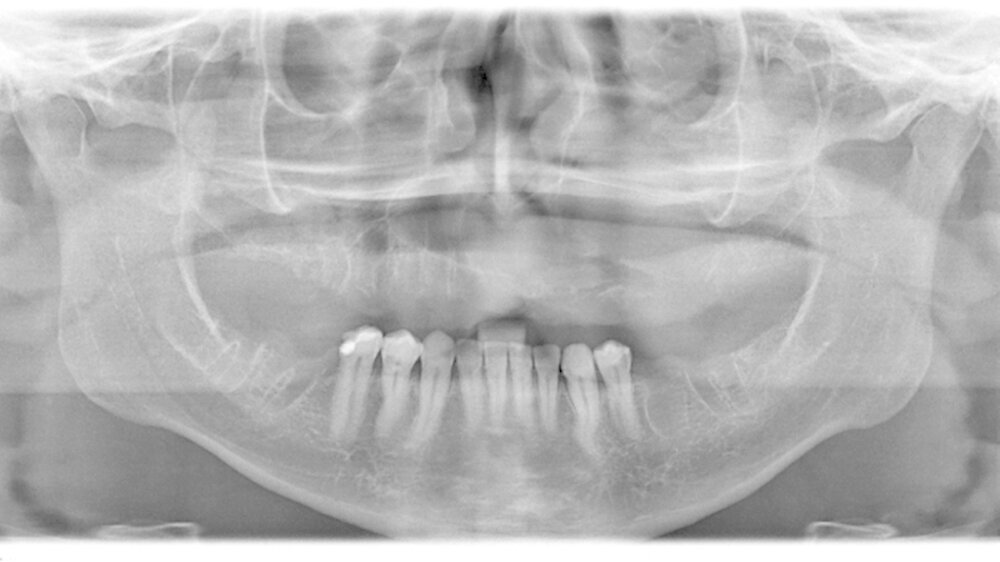

Der intraorale Zahnstatus beschreibt einen insgesamt sanierungsbedürftigen Zustand mit diversen nicht erhaltungswürdigen Zähnen im Unter- und Oberkiefer. Der Oberkiefer zeigte klinisch im zweiten Quadranten eine ausgeprägte palatinale Schwellung (Abbildung 2). Die Panoramaschichtaufnahme bestätigte den klinischen Verdacht auf eine ausgedehnte osteolytische Raumforderung im Oberkiefer. Diese erstreckte sich vom linken Oberkiefer die Mittellinie überschreitend, die gesamte linke Kieferhöhle einnehmend bis zur Regio 14 gehend (Abbildung 3). Durch den Hauszahnarzt konnte ein sechs Jahre zuvor erstellter Zahnfilm zur weiteren Diagnostik hinzugezogen werden.

Bereits damals wurde vom Hauszahnarzt eine Entfernung der noch umschriebenen Raumforderung dringend empfohlen. Der Zahnfilm zeigte ein zystisches Geschehen in der Regio 24 und 25 (Abbildung 4). Zur aktuellen weiteren präoperativen Diagnostik wurde eine Computertomografie angefertigt. In den coronalen Schnitten ist die die Mittellinien überschreitende Raumforderung bis zum knöchernen Nasenboden unter Einbezug der linken Kieferhöhle deutlich zu sehen (Abbildung 5a). Man erkennt insbesondere in den sagittalen Schnitten, dass die Raumforderung über zwei Drittel der linken Kieferhöhle beansprucht (Abbildung 5b).